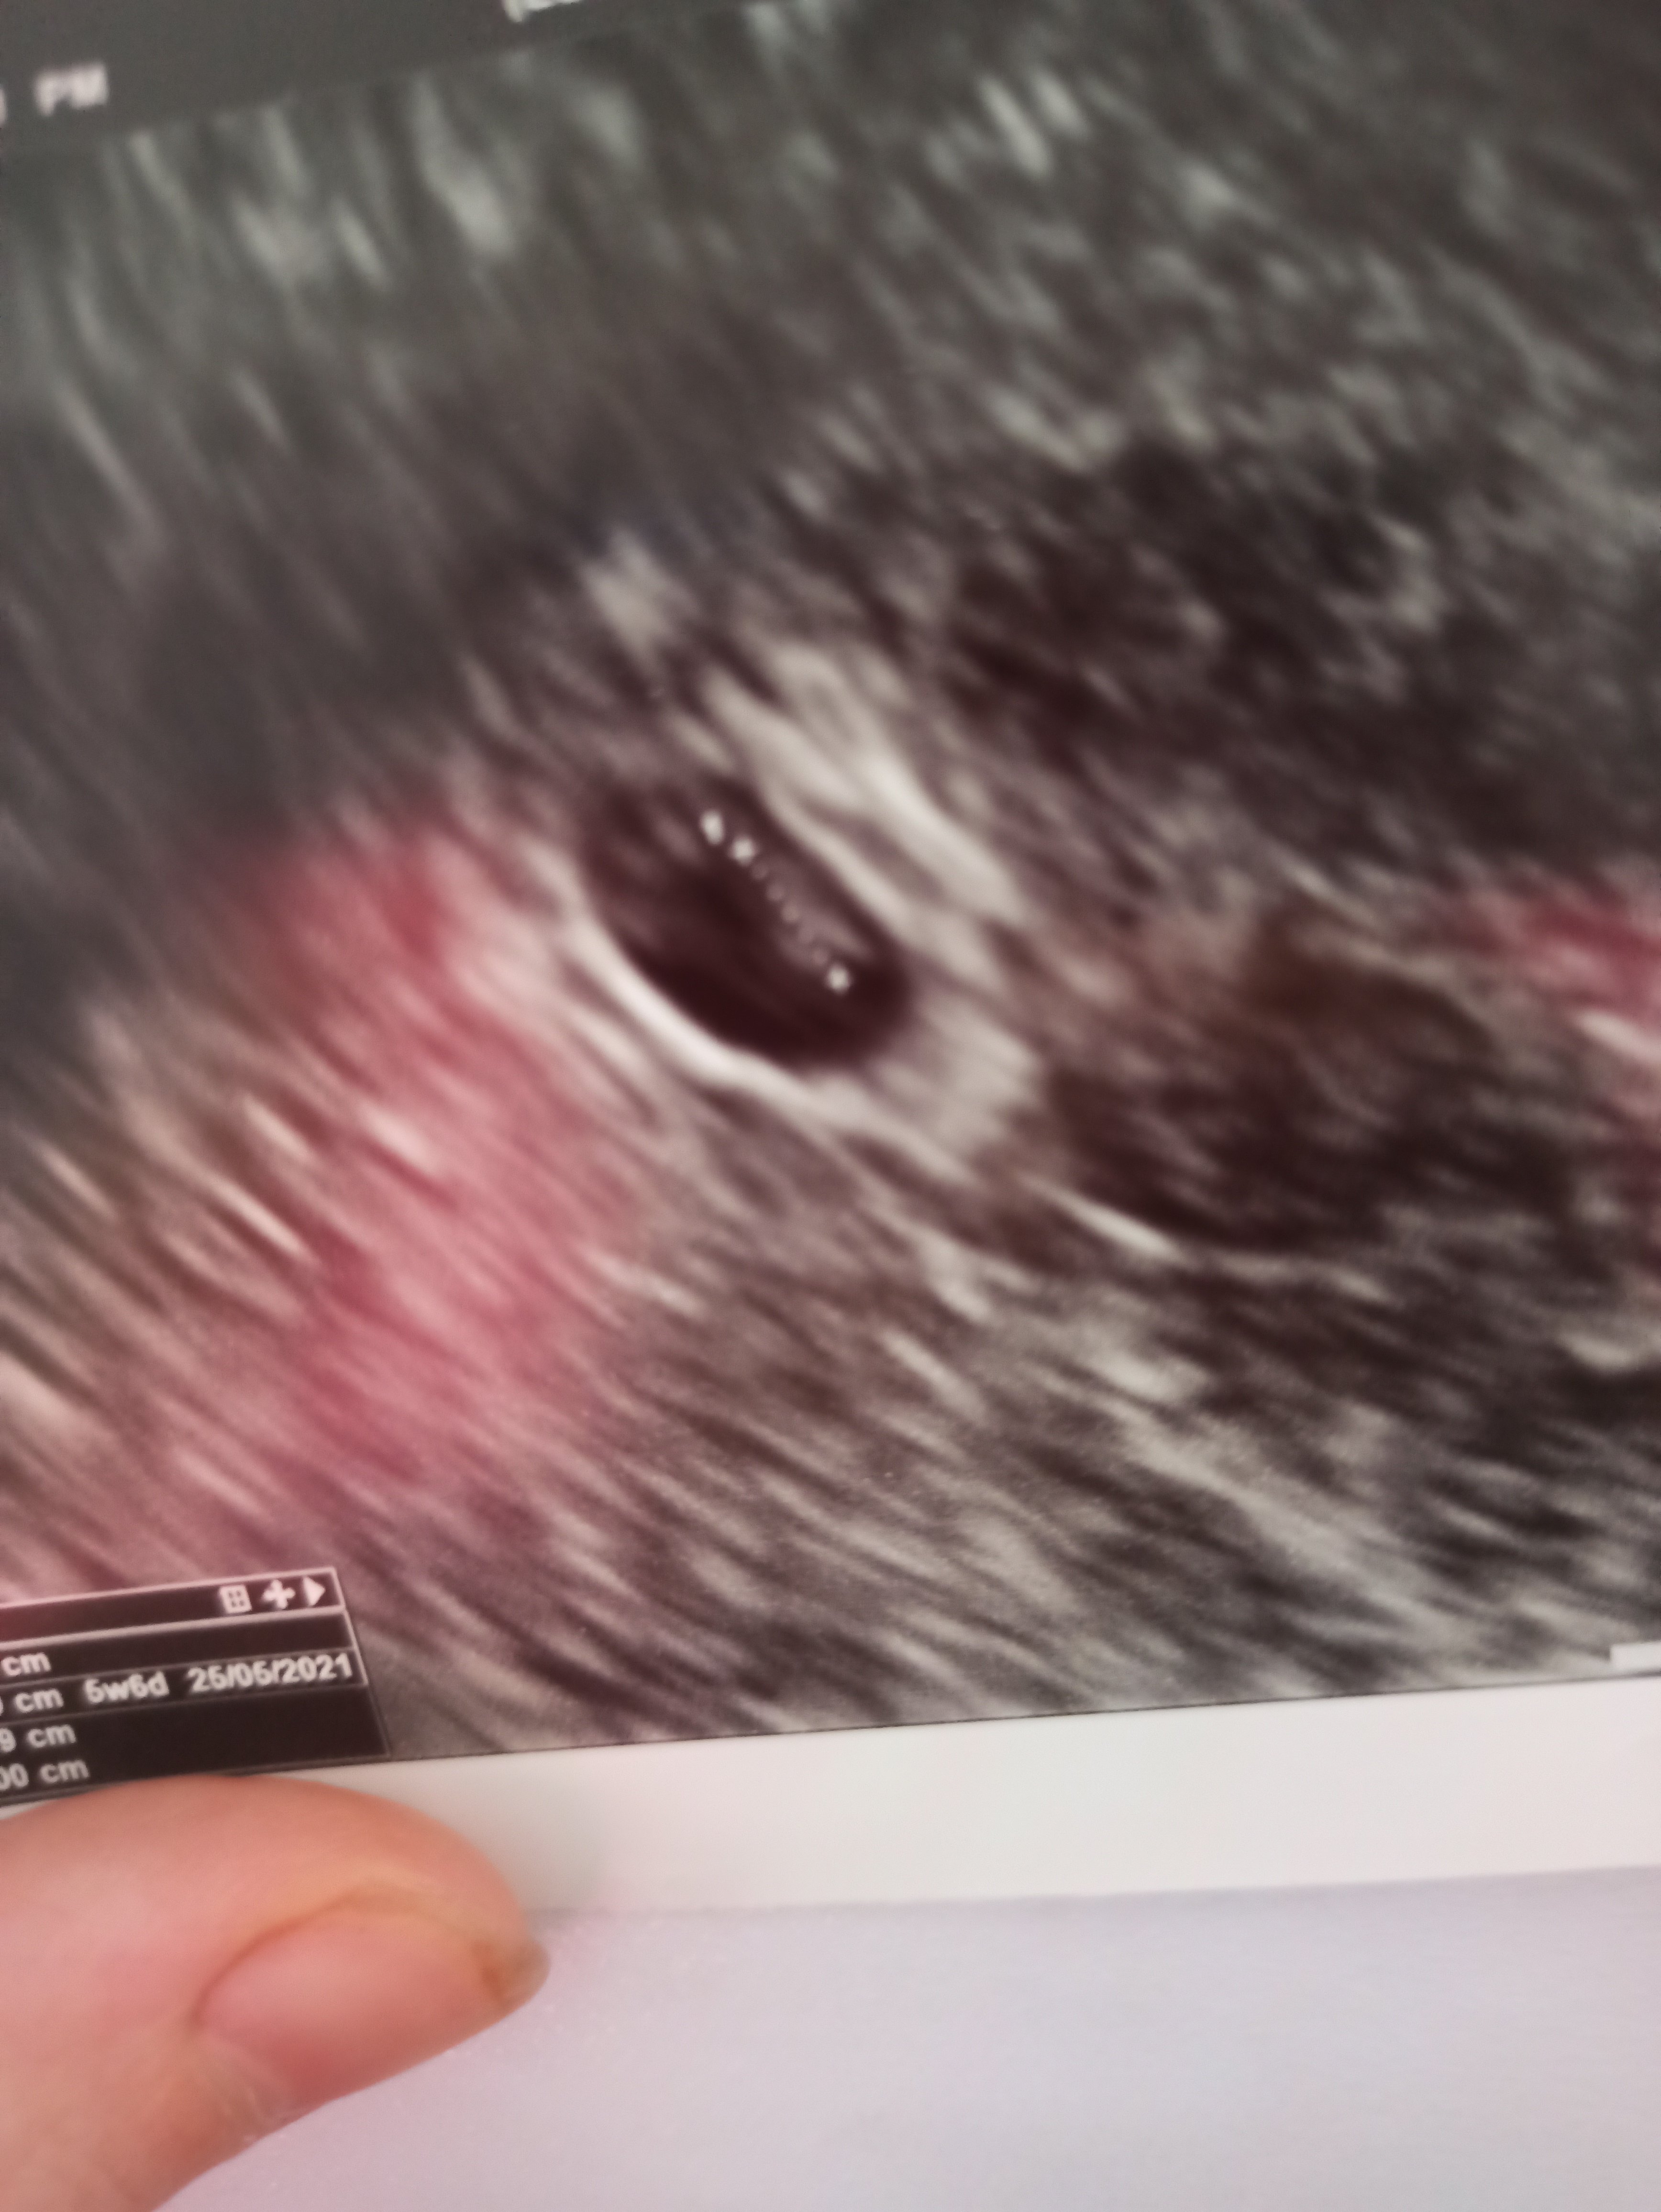

Hej, postanowiłam napisać tutaj, bo jako, że jesteście świeżo w temacie to pewnie się orientujecie. Jestem po 1 poronieniu, obecnie 7t, 0d. ale chyba nie jest dobrze, mam prawdopodobnie za duży pęcherzyk żółtkowy - 5.4mm a pęcherzyk ciążowy jest nieduży, natomiast zarodek CRL 9,1mm.

Bardzo dużo czytałam o tych pęcherzykach żółtkowych i niektore zrodla podaja, ze rozmiar powyzej 5.6mm to juz jest źle, inne ze rozmiar powyżej 6mm zwiastuje coś złego (oczywiscie tez w zaleznosci od tygodnia, pewnie w 11 tygodniu 6mm to jeszcze spoko). Natomiast u mnie to dopiero 7 tydz. 0 d. a skoro juz jest 5.4mm to jak bardzo podrośnie do 10 tygodnia na przyklad